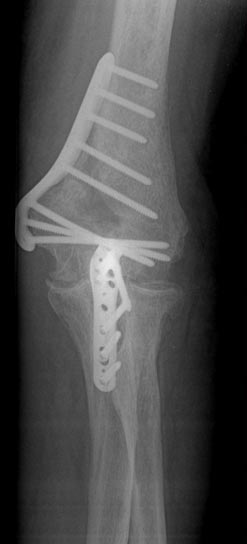

Post-Surgery

Repair of Condyle Fracture With Screw